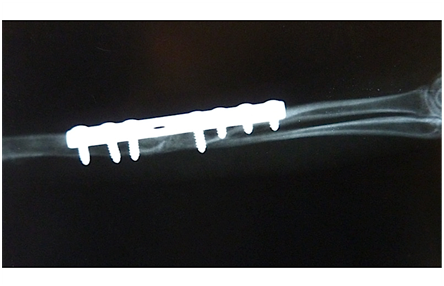

X-ray examination was performed after the surgery while animal was still anaesthetised. Another x-ray was performed 4weeks post surgery and showed complete healing of the radius with thinner remodelling callus but ulnar fracture line was still present. Bone callus was visible and smaller than in a preoperative x-ray. As a time goes on the primary or temporary callus was gradually replaced by mature lamellar bone, and the excess callus was resorbed. Soft tissue swelling and pain was not observed over fracture site. Palpatory there was no excesive callus present. Plate and screw heads could be palpated through the skin. Range of motion of the carpal joint was the same as on contralateral limb. Pronation and supination were possible and painless. Six weeks post operative x-ray showed that both radius and ulna healed completely Figure 2.

Figure 2 Osteosynthesis of radius with 2.0 Synthes stainless steel plate with 7 cortical 2.0 screws. Five weeks postoperatively fracture line is not visible, angulation is not present. Fused radius and ulna within healed fracture.